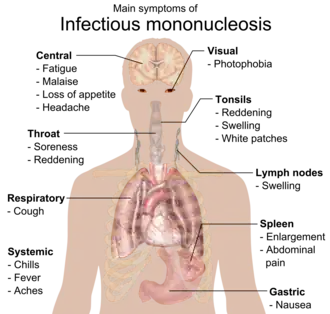

Infectious mononucleosis (IM, mono), also known as glandular fever, is an infection usually caused by the Epstein–Barr virus (EBV).[2][3] Most people are infected by the virus as children, when the disease produces few or no symptoms.[2] In young adults, the disease often results in fever, sore throat, enlarged lymph nodes in the neck, and fatigue.[2] Most people recover in two to four weeks; however, feeling tired may last for months.[2] The liver or spleen may also become swollen,[3] and in less than one percent of cases splenic rupture may occur.[6]

Signs and symptoms

The signs and symptoms of infectious mononucleosis vary with age.

In adolescence and young adulthood, the disease presents with a characteristic triad:[18]

- Fever – usually lasting 14 days;[19] often mild.[16]

- Sore throat – usually severe for 3–5 days, before resolving in the next 7–10 days.[20]

- Swollen glands – mobile; usually located around the back of the neck (posterior cervical lymph nodes) and sometimes throughout the body.[9][16][21]

Another major symptom is feeling tired.[2] Headaches are common, and abdominal pains with nausea or vomiting sometimes also occur.[18] Symptoms most often disappear after about 2–4 weeks.[2][22] However, fatigue and a general feeling of being unwell (malaise) may sometimes last for months.[16] Fatigue lasts more than one month in an estimated 28% of cases.[23] Mild fever, swollen neck glands and body aches may also persist beyond 4 weeks.[16][24][25] Most people can resume their usual activities within 2–3 months.[24]

The most prominent sign of the disease is often pharyngitis, which is frequently accompanied by enlarged tonsils with pus—an exudate similar to that seen in cases of strep throat.[16] In about 50% of cases, small reddish-purple spots called petechiae can be seen on the roof of the mouth.[25] Palatal enanthem can also occur, but is relatively uncommon.[16]

Complications

Spleen enlargement is common in the second and third weeks, although this may not be apparent on physical examination. Rarely, the spleen may rupture.[27] There may also be some enlargement of the liver.[25] Jaundice occurs only occasionally.[16][28]